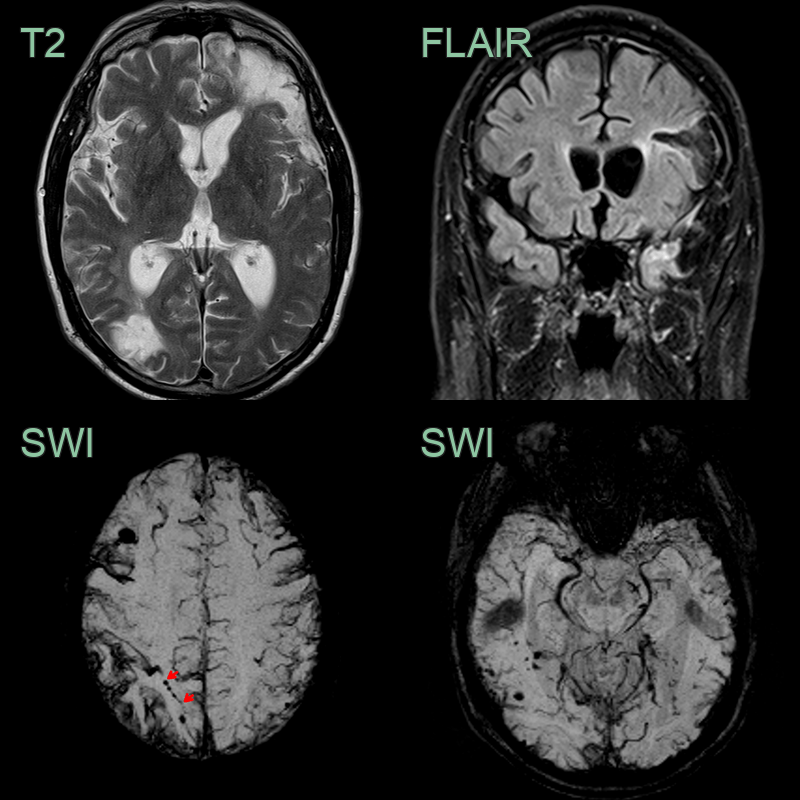

- MRI showed old parenchymal contusions in the left frontal and temporal lobes alongside an old contre-coup injury in the right occipital lobe.

- SWI showed extensive superficial cortical siderosis secondary to traumatic subarachnoid haemorrhage.

- There were many cortical or immediately subcortical microhaemorrhages. Some of the microhaemorrhages (e.g., in the right superior parietal lobe) were arranged linearly (red arrows).